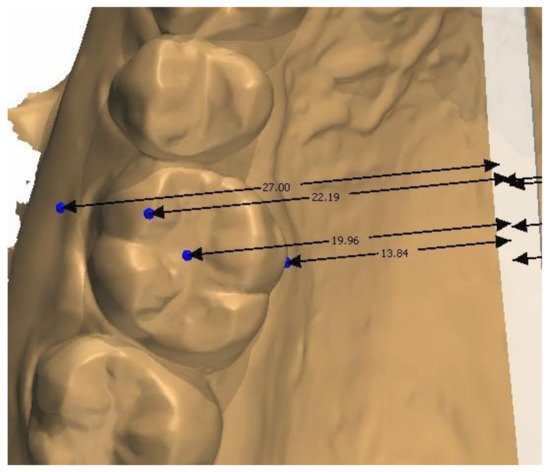

2.2. Methodology of Measurements